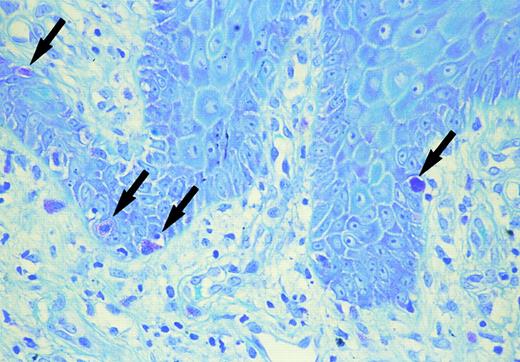

Mast cells in the basal layer of the epidermis (arrow) (toluidine blue).

Skin biopsy specimens were fixed with 10% formalin solution and were stained with hematoxylin-eosin and toluidine blue at a pH of 2.5, 4.1, and 7.0 to identify mast cells. Mast cells containing metachromatic granules were counted under high magnification of the ×400 power-fields of a light microscope. As the mast cells were most numerous in the papillary dermis or upper dermis of the MF lesion, the number of metachromatic cells was counted in 10 fields in this layer. Immunohistochemistry was performed with a standard avidine-biotin peroxidase technique (Nichirei Co, Tokyo Japan) using recombinant anti-SCF monoclonal antibody (Genzyme, Cambridge, MA) (dilution at a final concentration of 1:50). The sections were developed with 3-amino-9-ethylcarbazole as chromogen, counterstained with hematoxylin, dehydrated, cleared, and mounted. Negative controls were prepared by omitting of the specific antibody. SCF concentration in the serum before systemic chemotherapy was determined with a sandwich enzyme-linked immunosorbent assay (ELISA) kit (Amersham, UK). As controls, serum was obtained from 3 patients with infiltrative stage MF without either diffuse pigmentation or itching, and from 10 normal volunteers (5 males and 5 females; age range, from 44 to 60 years). Increased number of mast cells were observed in the upper dermis. The number of mast cells in the upper dermis (133.2 ± 15.6/mm2 in case 1, and 113.4 ± 10.1/mm2 in case 2) was significantly higher than that of either 3 infiltrative stage MF (44.6 ± 7.8/mm2 ) (P < .005) or normal healthy skin (38.5 ± 9.1/mm2 ) (P < .005 in case 1 and P < .005 in case 2). In both cases, intra-epidermal mast cells were shown by toluidine blue staining in a specimen from thigh in case 1 and from buttock in case 2 (Fig 1). Clinically, both lesions showed marked infiltration or lichenification. Double staining of toluidine blue and Periodic acid-Schiff (PAS) staining showed mast cells to be above the basal membrane. Immunohistochemistry demonstrated positive perinuclear staining in a cytoplasmic pattern for SCF on tumor cells, mast cells, endothelial cells, and keratinocytes in the acanthotic epidermis in both cases. The serum SCF concentration was increased (1,640 pg/mL in case 1 and 1,250 pg/mL in case 2) as compared with that in the 3 patients with MF, but without any diffuse pigmentation or itching (863 ± 145 pg/mL) as well as the normal volunteers (748 ± 256 pg/mL).